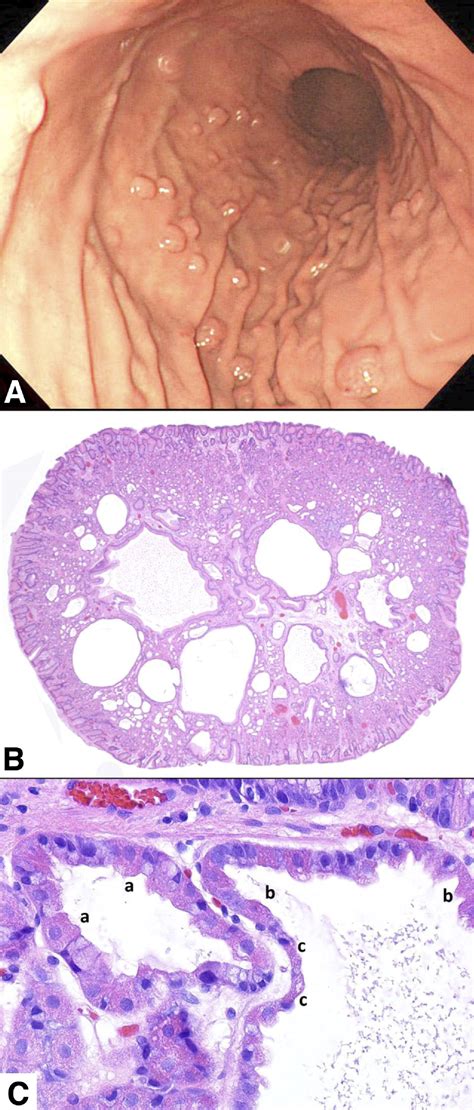

To better understand polyps in oesophagus, it is helpful to categorize them based on their histological characteristics. Not all polyps are the same, and their potential for becoming malignant differs based on their classification:

• Inflammatory Fibroid Polyps: These are often associated with chronic inflammation and are typically benign.

• Squamous Papillomas: These are wart-like growths that are often associated with the human papillomavirus (HPV) or chronic mechanical irritation.

• Glandular Polyps: These arise from the mucus-secreting glands of the esophagus and are usually related to conditions like Barrett’s esophagus.